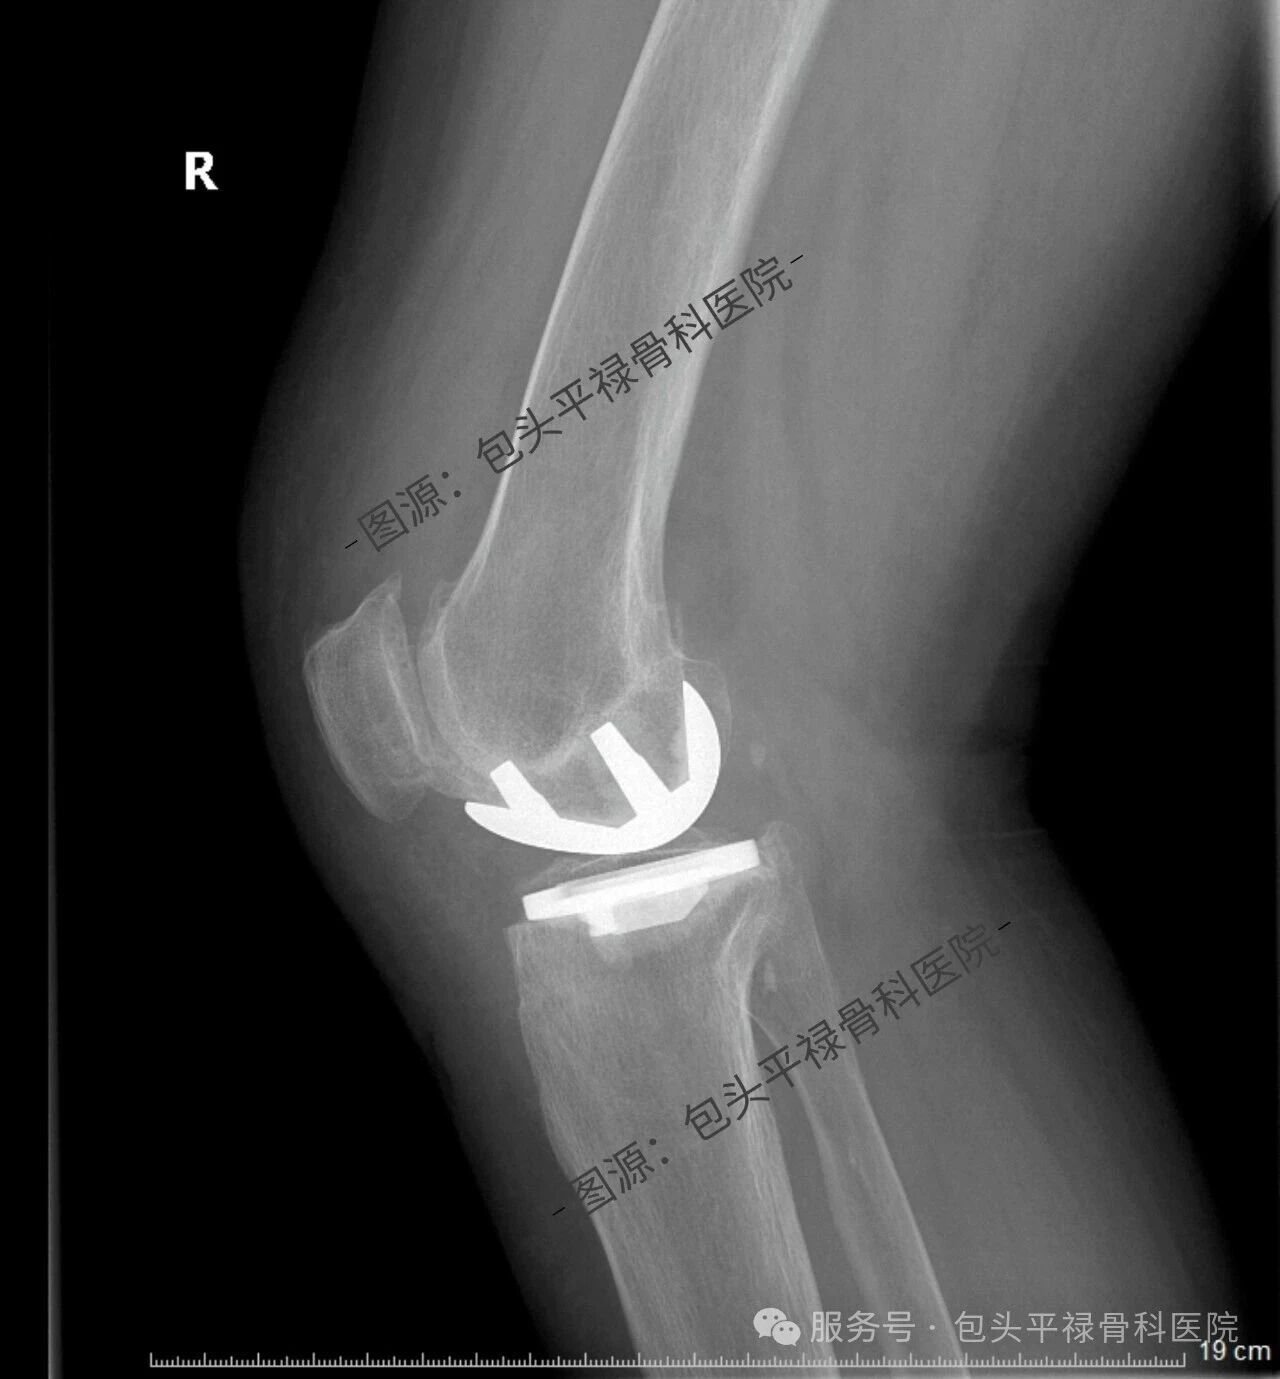

其实,现代医疗技术日趋精准,如果患者的关节炎只局限于膝关节的一个部分(单侧间室),那么TA很可能适合一种更为精准、创伤更小的手术——膝关节单髁置换术。

膝关节单髁置换术相当于“局部翻新”,就是只置换“坏掉房间”的磨损表面,仅将受损的软骨和部分骨质去除,替换为人工假体,而完好的软骨、交叉韧带及其他结构都得以最大程度的保留。